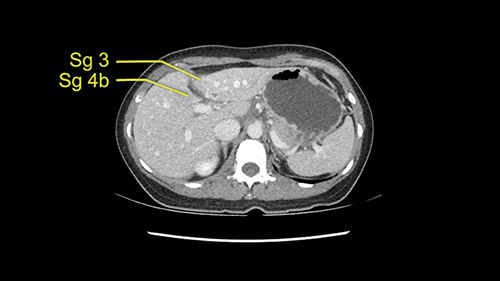

So if we look at the CT scan, on the axial, it’s a larger lesion. It’s about 6 or 7 or 8 centimeters. So it does look a bit threatening in terms of its resectability but if you really drill down deeply into the anatomy, and I think the coronal [imaging] is even better, you can see that the entire mass is on the patient’s left side of the falciform ligament. So it’s really only a left-sided tumor and not even really a left-sided tumor because Segment 4 is uninvolved anatomically.

As I review the CT scan, we have both arterial and venous phases, the tumor is obvious. But I’ll start by saying that the liver itself does not appear to be cirrhotic to my eye. It’s got a normal contour and allied to that, that I do not see evidence of portal hypertension. The spleen is normal, there’s no collateral vessels. The tumor itself, I measured maximally at about 11 centimetres in diameter and I’m told the alpha fetoprotein is very high (over 10000), which is entirely consistent with this being a solitary hepatocellular carcinoma that is very exophytic. It seems to emanate off the inferior margin of Segment 3 (because that’s the falciform). I’ll start by saying that this is not transplantable. The tumor exceeds our guidelines for transplantation, but it's likely resectable based on normal liver and no portal hypertension.

So the issue with regards to resection. A left sided tumor. I believe I can see the falciform ligament right here so we’re looking at a resection of Segments 2, 3 of the left lobe of the liver. The left portal vein is right there. I think we’ll be wiser to take the left portal vein and therefore get well into Segment 4 and do a left hemihepatectomy. Certainly, one does not need to take the middle hepatic vein; it’s miles from the tumor.

We note that the tumor is pushing on the gallbladder but I think that’s probably external for the most part. I think that’s extrahepatic. I believe that Segment 4b is probably free of tumor. I’d have to say that it's tempting, particularly looking at the coronals, to consider a very limited resection. Where you’d just chip it off the bottom of Segment 3 and do a limited Segment 3 resection. I’d be concerned about the oncologic margins. I believe that the best oncologic operation will be to take the left portal vein to get this. Certainly, she’s got plenty of liver and she’d be able to sacrifice Segments 2-3 of the left lobe of the liver. It’s not necessary to take too much of thus of Segment 4a. But once one takes the portal vein, that will be compromised. So I would do a left hemihepatectomy on this woman.

Hi my name is Sedat Karademir. I’m from Ankara Guven Hospital and I’m an HPB and transplant surgeon. We are discussing about the case I reviewed the CT of 41 year old lady with a suspected hepatoma in the left lateral segment. Presumably its Segment 3. It looks like a big tumor sitting exophytically mostly out of the liver and pressing on the surrounding organs, but it doesn’t look like any invasion there. In this situation, according to the venous and arterial anatomy, it looks like this will be a Segment 2 and 3 resection.

The tumor is so close to the falciform ligament, I had a question mark about the Segment 4b relation between segment 4b and segment 3. In a normal resection of segment 2 and 3, we would be keeping on the left side of the falciform ligament and start getting segment 3 and 2 portal pedicles but in here its getting so close. So oncologically, 4b should be checked during the OR.

The other thing I would do in this case is to certainly to assess the coronal phase as we can see in the coronal phase, this tumor looks like it's growing from Segment 3, and again I don’t think there’s involvement of the right side of the liver or even on Segment 4.